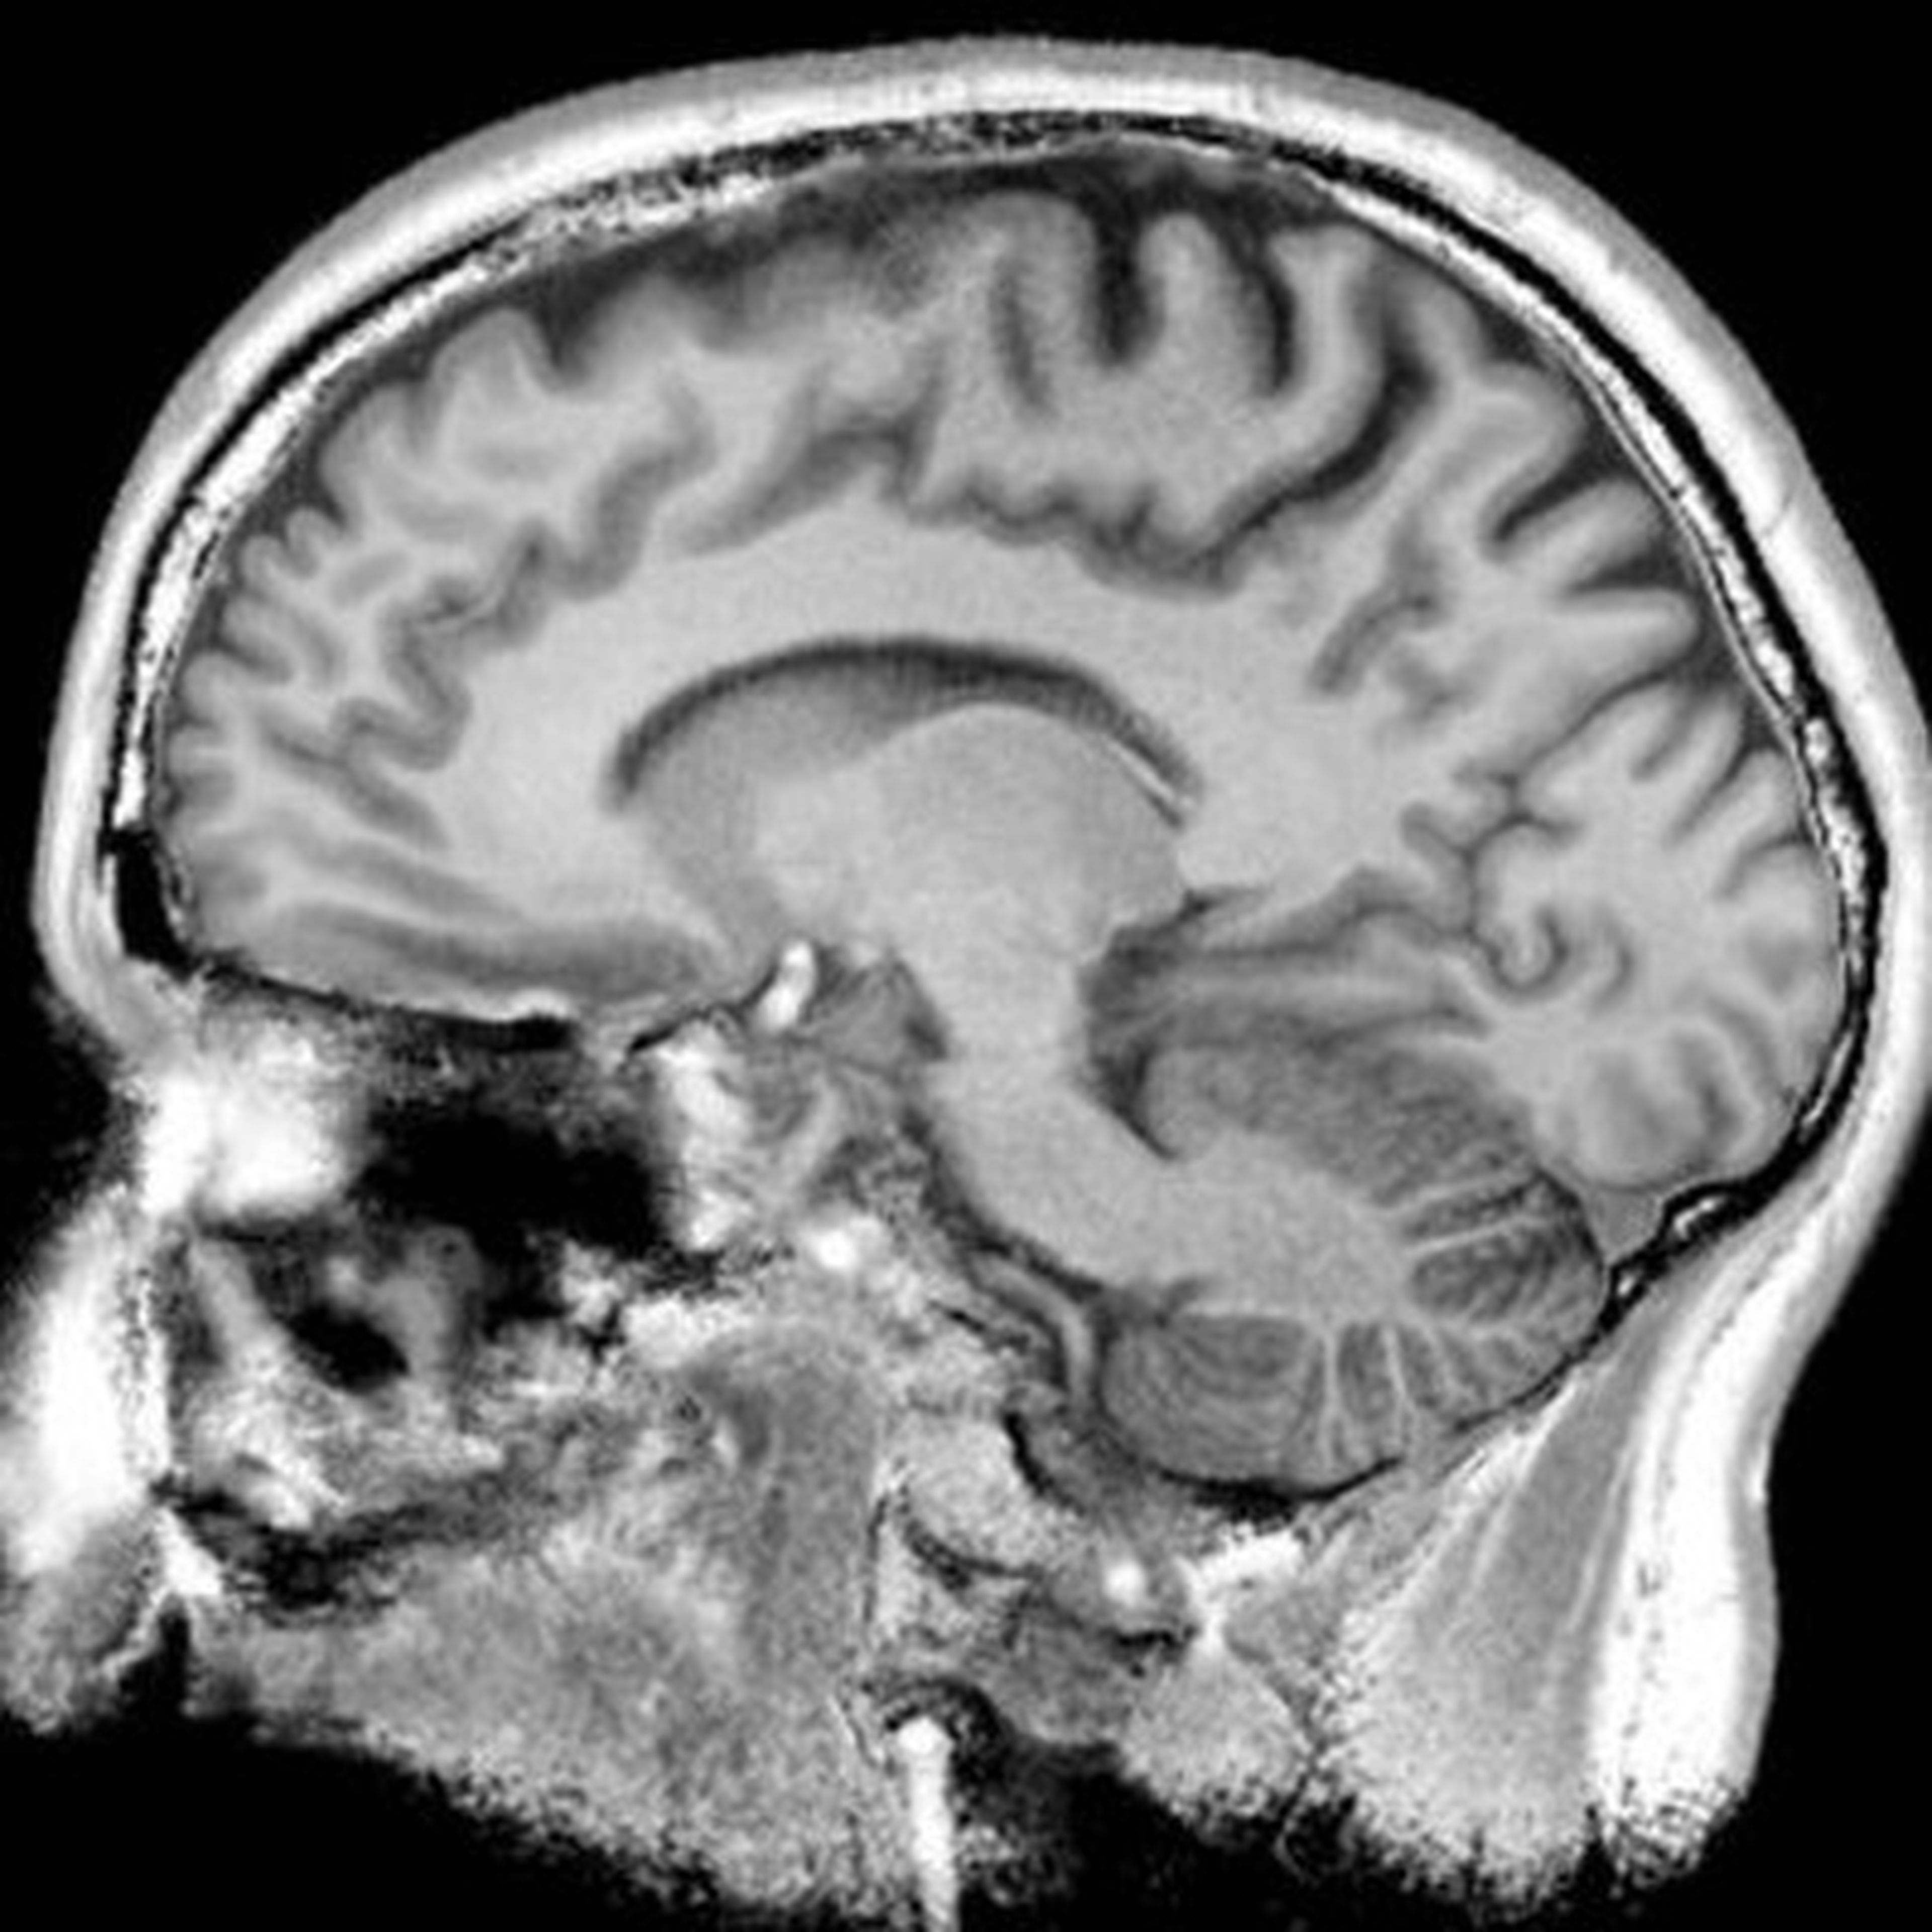

My research focuses on developing advanced AI and deep learning methods for medical imaging to improve automated disease diagnosis, monitoring, and clinical decision support across modalities such as MRI, CT, ultrasound and ophthalmic imaging.

His research emphasizes explainable and uncertainty-aware AI, spanning unsupervised and self-supervised representation learning, multi-modal and longitudinal image analysis, radiomics, artifact detection, and federated learning, with applications across MRI, CT, ophthalmic imaging, and image-guided surgery. He has authored more than 100+ peer-reviewed publications, contributed to three patents, and led or co-led projects on topics such as epistemic and aleatoric uncertainty quantification in 3D segmentation, AI-enabled cone-beam CT reconstruction, neuroendoscopic guidance, retinal image analysis, and automated radiomics pipelines for vascular malformations and pancreas cancer risk stratification. He frequently reviews papers for top level journals and is an Associate Editor of the Journal of Medical Imaging. Prior to joining the University of Alberta, he held faculty and research roles in Computer Science, Radiology, Ophthalmology, and Gastroenterology at Johns Hopkins, co-directed a Radiology AI Lab, and directed the Center for the Advancement of Medical AI, a not-for-profit initiative supporting collaborative imaging and large language model applications in healthcare.